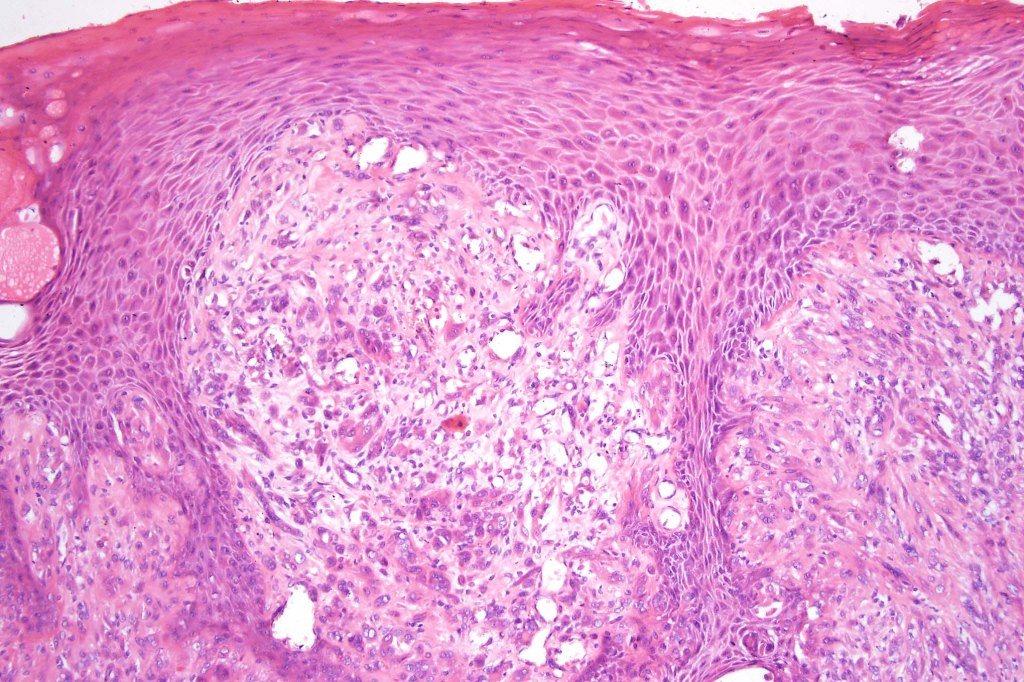

•Sharply circumscribed (begins and ends with a nest), symmetrical dome-shaped lesion. Symmetry is both horizontal and vertical (see image below)

•Wedge-shaped with the base uppermost or sometimes plaque-shaped silhouette

•Superficial vascular ectasia very frequently present

•Junctional nests often vertically orientated, dyscohesive with a surrounding retraction artifact

•Pleomorphism is almost invariable but affects all of the population to the same extent i.e., the cells & nuclei all look very much the same